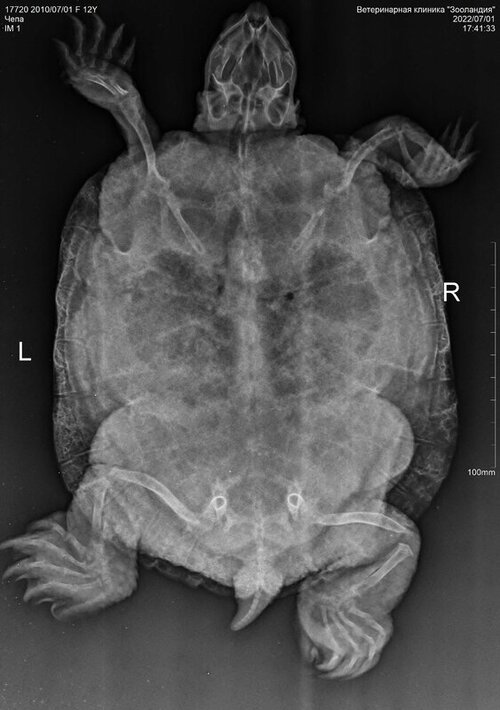

13. 12 лет, вес 1013 гр, ничего не ест, слабая, почти всегда находится на суше, открывает рот и надувает шею шариком, припухла, чешет нос лапкой, голова чаще лежит на островке. Болеет неделю, но вялость стала проявляться чуть раньше. Нашла в городе вет. врача, в сферу интересов которого входит лечение рептилий (не герпетолог), но ближайшая консультация возможна только через неделю. Чтобы не терять время, сделала рентген, уколола один раз 0,5 мл элиовита в мышцу ягодицы и через день колю борглюконат кальция 1 мл подкожно в бедро.

Вам тут нужно брать онлайн консультацию у герпетолога - у наших в телеграмм канале стоит 300р, оплата после консультации. Потому что из того, что я вижу - у черепахи практически полностью пережаты лёгкие и тут лечить должен врач. К сожалению я ничем помочь не смогу, потому что всё серьёзно.